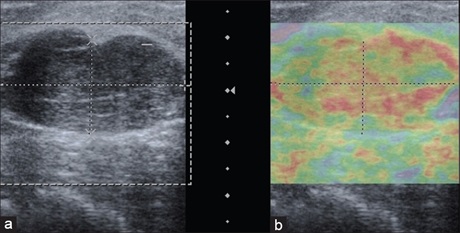

Results and Conclusion: The lesions were classified on elastography using scoring system described by Itoh et al., 2006 with elasticity score of 1,2,3 as benign and score of 4 and 5 as malignant. The sensitivity of USE was found to be 88.57% with specificity of 90.32% and positive predictive value of 91.18%. Thus, we conclude that in the present scenario, USE can be used in early diagnosis and differentiation of breast masses into benign and malagnant and henceforth, can be influential in reducing the number of breast biopsies.